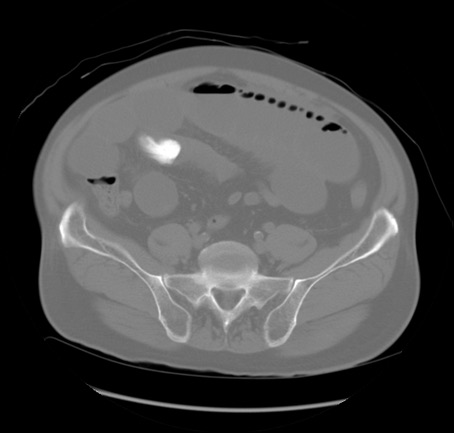

症例20(横断像)

【症例】 60歳代男性

【主訴】 腹部膨満、嘔吐

【現病歴】5日前頃より倦怠感を認め食事量減少し4日前の朝嘔吐、食事摂取困難となった。 3日前近医受診し点滴施行され整腸剤などを処方された。 当日他院を受診し、腹部膨満著明、炎症反応の上昇(CRP10.8、WBC11200)あり、紹介受診となる。

【身体所見】 意識JCS1 受け答えがはっきりしないBP 111/57mHg、 P 67bpm、、BT35.2°C、SpO2 97%(RA)、 腹部:膨隆、打診で鼓音あり、全体的に圧痛有り、腸蠕動音(-)、反跳痛ははっきりせず。

【データ】WBC 11400、CRP 14.20